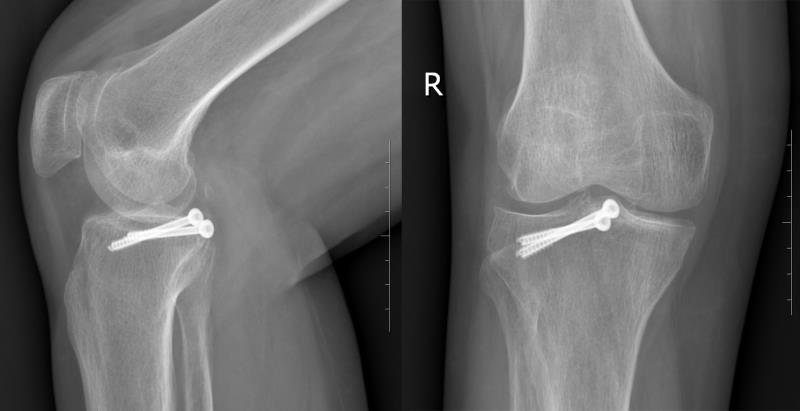

术后复查右膝关节CT及三维重建,提示骨折能够达到解剖复位,内固定位置合适

术后3月复查X线片提示骨折达到骨愈合

术后,患者右膝关节伸直位固定1个月后,在支具保护下逐渐负重行走,术后8周便去除支具完全负重行走。术后3个月复查,右膝关节X线片检查提示右膝后交叉韧带止点撕脱骨折达到骨愈合,右膝关节功能各项指标接近术前,大限度的恢复了患者右膝关节功能。经过8个月的随访,患者及其家属对手术效果非常满意,取得了良好的临床效果。